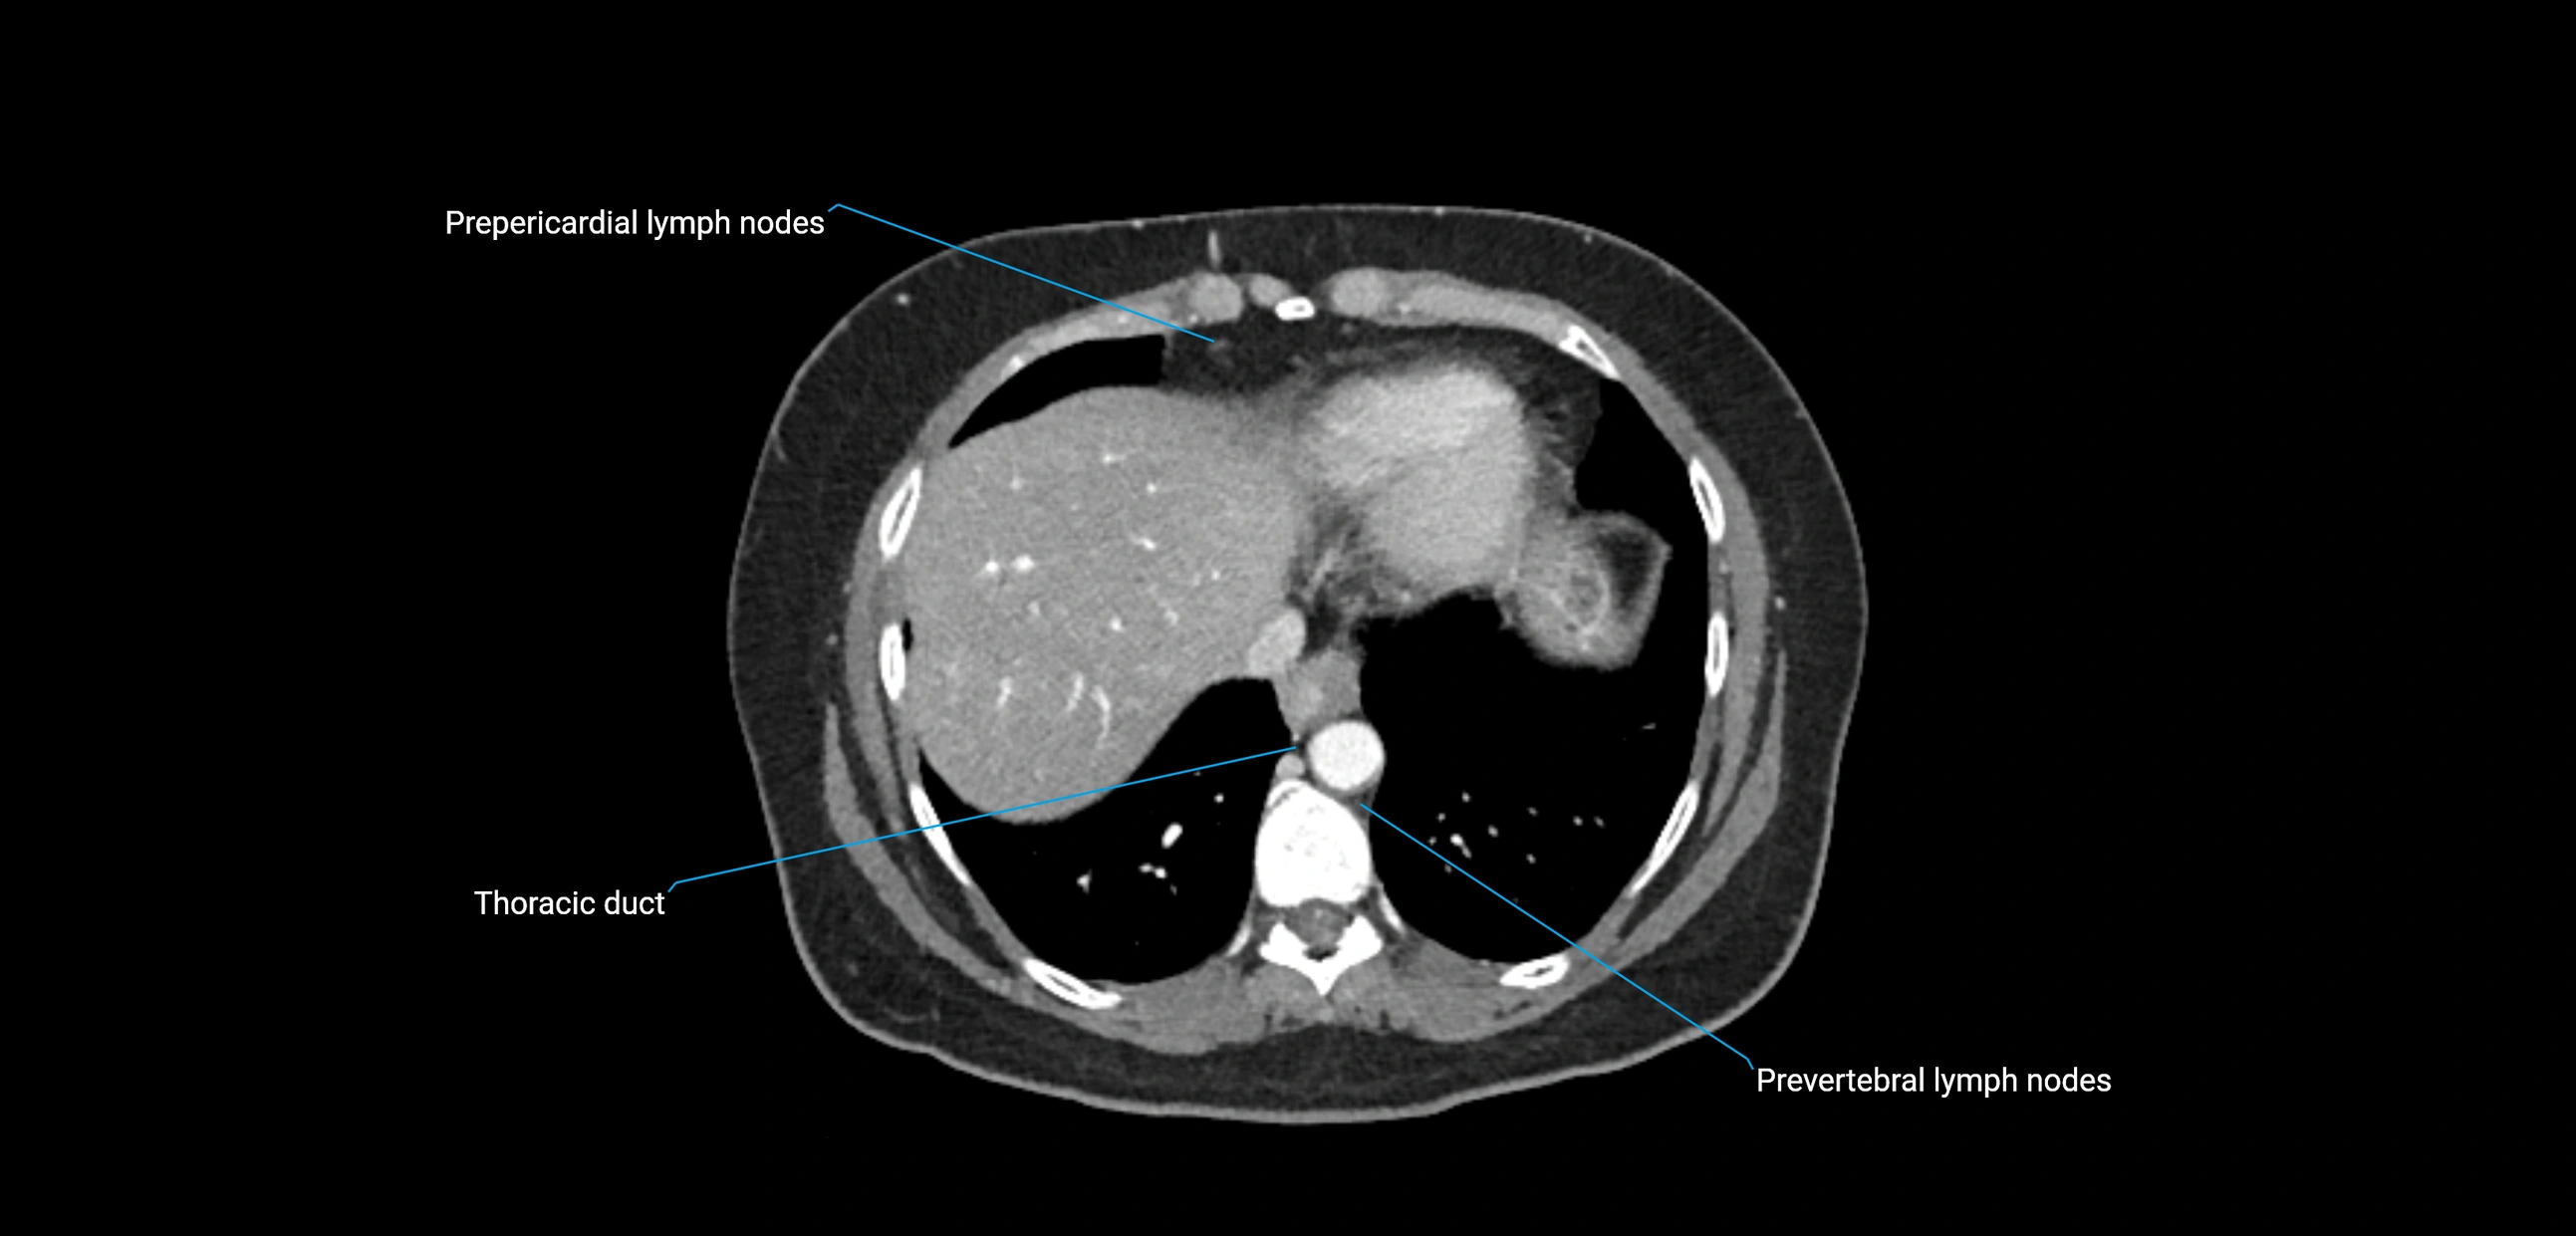

CT Appearance

CT Pre-Contrast:

• Nodes appear as soft-tissue density nodules adjacent to the aorta and IVC

• Calcification may be seen in chronic infections (e.g., tuberculosis)

CT Post-Contrast:

• Normal nodes enhance homogeneously

• Malignant nodes may show heterogeneous enhancement, central necrosis, or conglomerate formation

• Size >1 cm short axis is suspicious, though morphology and distribution are equally important